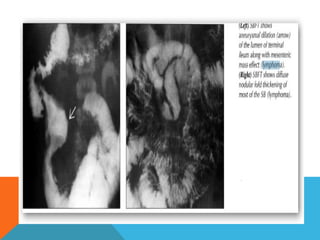

Duodenal Lymphoma---Bulky Soft Tissue Mass

Infiltrating Submucosa

Small Intestinal Mass